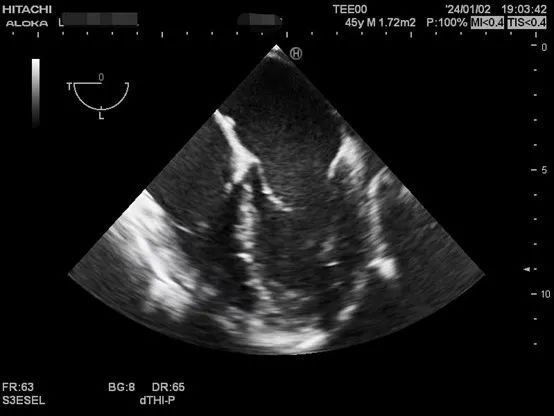

以下是肝移植术中TEE监测的图像。

肝硬化患者术前合并症较多,术中血流动力学波动剧烈,围术期可能发生严重低血压、心内血栓形成、肺栓塞、左室流出道梗阻、心室收缩舒张功能不全等危急事件,给麻醉管理带来巨大挑战。TEE是将超声探头放在食管中段或胃底,从心脏后方持续观察心脏结构和功能,避免肺气对成像的影响,图像清晰且不影响手术的操作,是肝移植术中重要的监测手段之一。美国心脏超声协会及美国心血管麻醉医师学会均推荐肝移植术中常规使用TEE。目前美国各大移植中心术中麻醉科术中常规使用TEE进行持续监测。